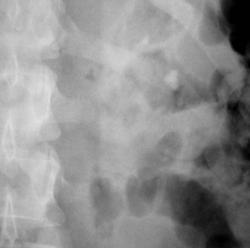

Иллюстрации 6, 7. После введения контрастного вещества функция с обеих сторон. Слева почка обычного расположения, формы и размеров. Вышеописанные конкременты располагаются в эктазированных малых чашечках. Мочеточник обычного калибра, прослеживается на всем протяжении.

Иллюстрации 8, 9. Четко дифференцируются конкременты в малых чашечках левой почки. Справа определяется контрастирование малых чашечек в виде нечётко очерченных «лужиц».